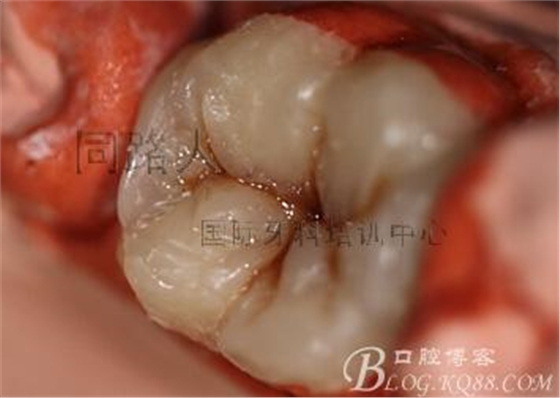

首先是嵌體的牙體預備

這個是比較”正常“的牙體預備,這方面相信大家已經看過了很多資料聽過了很多課,在此不再多言。在此提醒保留髓壁和齦壁的高度差很有必要。很多軸角轉折處的圓緩處理仿佛太極一般化解外力……牙齒預備也可以很”美學“。

這個是比較極端的高嵌體的牙體預備

我不推薦大家這么做,除非沒有選擇。挑戰(zhàn)極限就意味著你要承擔著失敗的挫折感。